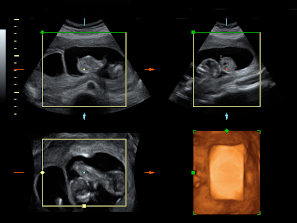

Vemos tres planos de un embarazo de trillizos en ecografía 2D en diferentes cortes de imagen. Lo que vemos en 3D es lo que los ecografistas conocen como "un queso", es decir el embarazo visto en tres dimensiones desde una perspectiva determinada. Lo que realmente esconde ese peculiar queso es un embarazo de trillizos: un feto independiente, separado de sus hermanos por una membrana.

Ecografía Embarazo 2D y 3D Semana 12 - ANOMALÍAS CROMOSÓMICAS